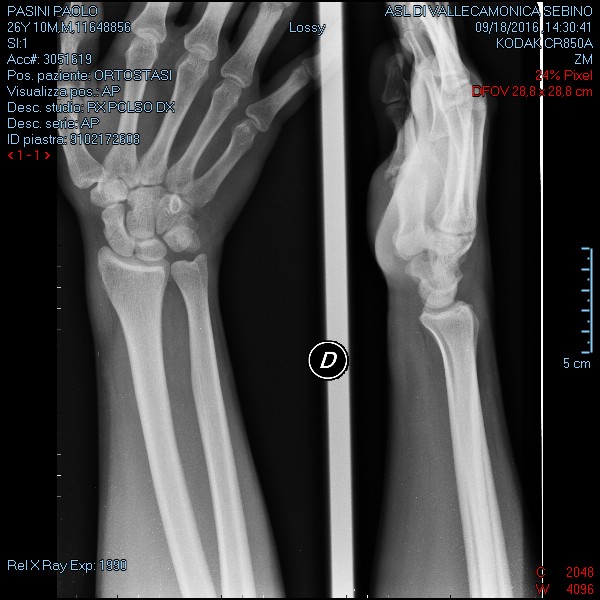

Una decina di giorni fa in seguito ad una caduta mi sono fratturato lo scafoide della mano destra.

E' una frattura molto composta, si nota a malapena nelle lastre.

Grazie mille per la risposta, le invio la lastra dove si vede la frattura.

7048.JPG

Viste le radiografie : ok è composta e forse incompleta . Metta il tutore con primo dito incluso e non lo levi più per 4 settimane . A presto